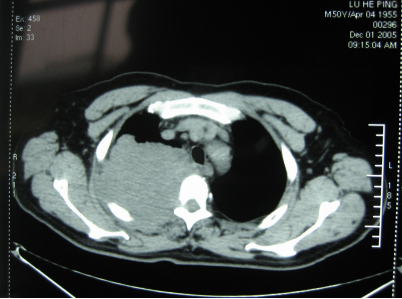

2003年魯叔便開始出現(xiàn)右上肢活動障礙,手不能提重物,后來發(fā)現(xiàn)手不能持物,上肢麻木疼痛,一開始魯叔還以為是頸椎或肩周炎有問題,并沒有放在心上,只是到當(dāng)?shù)蒯t(yī)院以肩周炎治療并無好轉(zhuǎn)。因疼痛加劇2004年11月魯叔去了益陽某醫(yī)院做檢查,CT顯示右上肺占位病變,考慮有肺癌的可能,做了兩次穿刺檢查但并沒有找到癌細(xì)胞。2005年12月1日魯叔來到了湖南省某大醫(yī)院就診,PET/CT檢查確診為右肺尖癌,同時第1后肋及鄰近胸椎侵犯,硬膜囊受壓,前后放療共20次,然而花了很大一筆錢卻療效甚微。

手術(shù)前CT顯示

“腫瘤大小約10×10cm,雖然已經(jīng)錯過最佳治療時間,但所幸來得及時,不然就真的無力回天。”當(dāng)天徐克成榮譽總院長、牛立志院長針對魯叔的病情組織專家會診,決定1月7日采用冷凍消融治療術(shù)+碘粒子療法為魯叔治療。